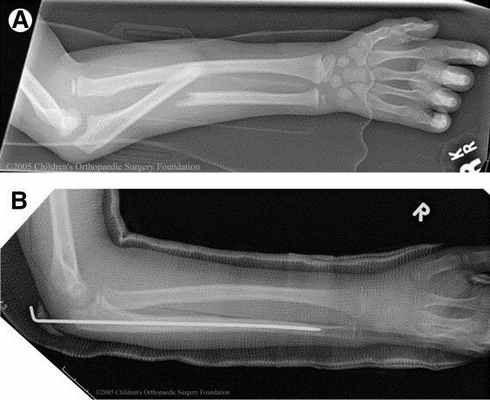

Остеосинтез лучевой/локтевой кости штифтом (стержнем)

Лучевая и локтевая кости по строению изнутри полые. И если пластина ставится на кость, то штифт вводится внутрь кости. Для установки штифта делаются несколько небольших разрезов (проколов кожи) - в области лучезапястного и локтевого суставов. Удаляют штифты примерно через год. Полноценные нагрузки, в т. ч. Спортивные, вне зависимости от выбранного метода остеосинтеза, можно начинать не менее чем через три месяца.

Переломы без смещения или с незначительным смещением в этой области достаточно редки, поэтому большинство подобных переломов требует оперативного лечения. Оно заключается в фиксации отломков (остеосинтез). Возможные варианты фиксации - установка пластины на кость или специальных штифтов (стрежней) внутрь кости. Метод выбирается по показаниям – в зависимости от величины отека, смещения отломков и других факторов (возраст, род занятий пациента).